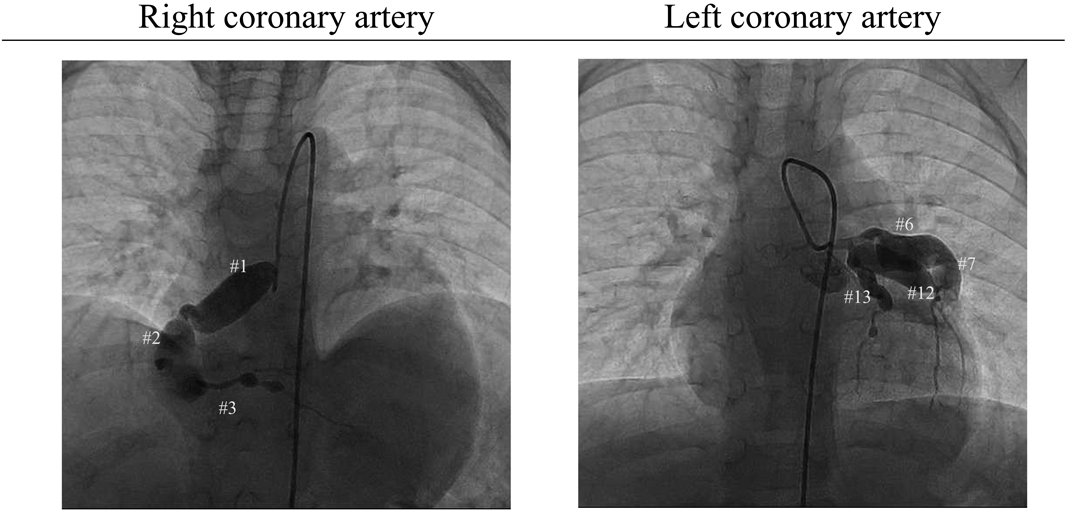

Previous episodes: The patient had developed KD 2 months prior to the AMI event this time. Having suffered from fever initially, he saw a doctor at a local hospital on day 3. He was diagnosed with cervical lymphadenitis, because of bilateral cervical lymphadenopathy, and treated with ceftriaxone. The symptoms, however, did not improve. Bilateral conjunctivitis was noted on day 4 and erythema of the palms and soles, skin rash, strawberry tongue, and reddened lips developed on day 5. At that stage, he was diagnosed as KD. Coronary arterial lesions were absent on echocardiography. This patient was treated with IV high-dose immunoglobulin, IV prednisolone, and oral aspirin. His body temperature decreased once, but rose again on day 6. IV high-dose immunoglobulin was repeated on day 7. Despite these treatments, his body temperature did not normalize. Subsequently, cyclosporine A was administrated on day 8 and the symptoms improved. Echocardiography on day 10 showed bilateral coronary arterial lesions that worsened on day 12. With these findings, the patient was referred to the regional medical center. Although there were no longer symptoms of KD, the C-reactive protein (CRP) levels did not settle, and he was treated with infliximab. Dipyridamole was given as an antithrombotic agent. Echocardiography on day 14 showed giant coronary artery aneurysms and IV heparin was started. His body temperature rose again; plasmapheresis was carried out from day 17 to 20. After the treatment, fever or abnormal CRP did not recur. He was discharged on oral warfarin because of the giant coronary artery aneurysms that remained. Coronary angiography a month after the KD onset illustrated significant coronary artery aneurysms ranging from 4.0 to 12.9 mm in diameter (Fig. 1).

Fig. 1 Coronary angiography images 1 month after the onset of Kawasaki disease in the previous institution. They show coronary artery aneurysms as follows: #1 (segment 1), 10.4 mm; #2, 9.8 mm and 12.9 mm; #3, 4.0 mm; #6, 3.2 mm; #7, 9.8 mm; #12, 6.8 mm; and #13, 4.2 mm